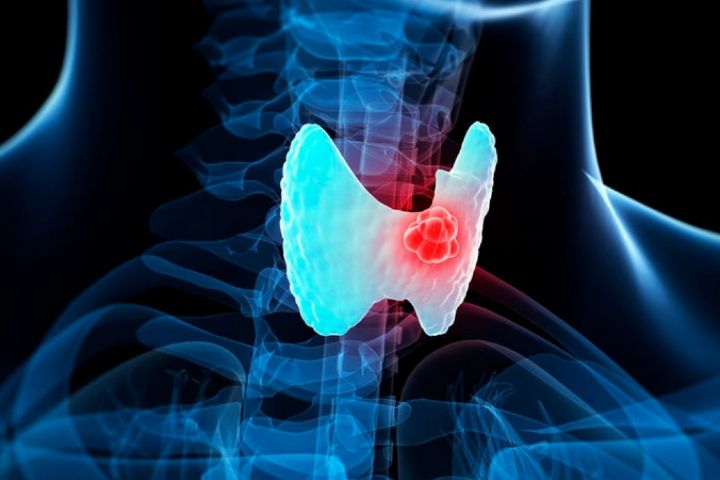

به گزارش بهداشت نیوز، دکتر «ساسان شرقی»، متخصص غدد و متابولیسم در گفتگو با برنامه «خونه زندگی» رادیو سلامت گفت: تیروئید، غده ای است پروانه ای شکل در جلوی گردن در پایین حنجره و بالای استخوانهای ترقوه. تیروئید، دو نوع هورمون ترشح می کند که وارد خون می شود و آن ها باعثِ سوخت و سازِ سلول های بدن اعم از پوست، عصب و ... می شود. هدف اصلی تیروئید، تنظیم سوختوساز بدن است که اگر نتواند این کار را به درستی انجام دهد طبیعتا سوخت و ساز بدن دچار مشکل می شود که این